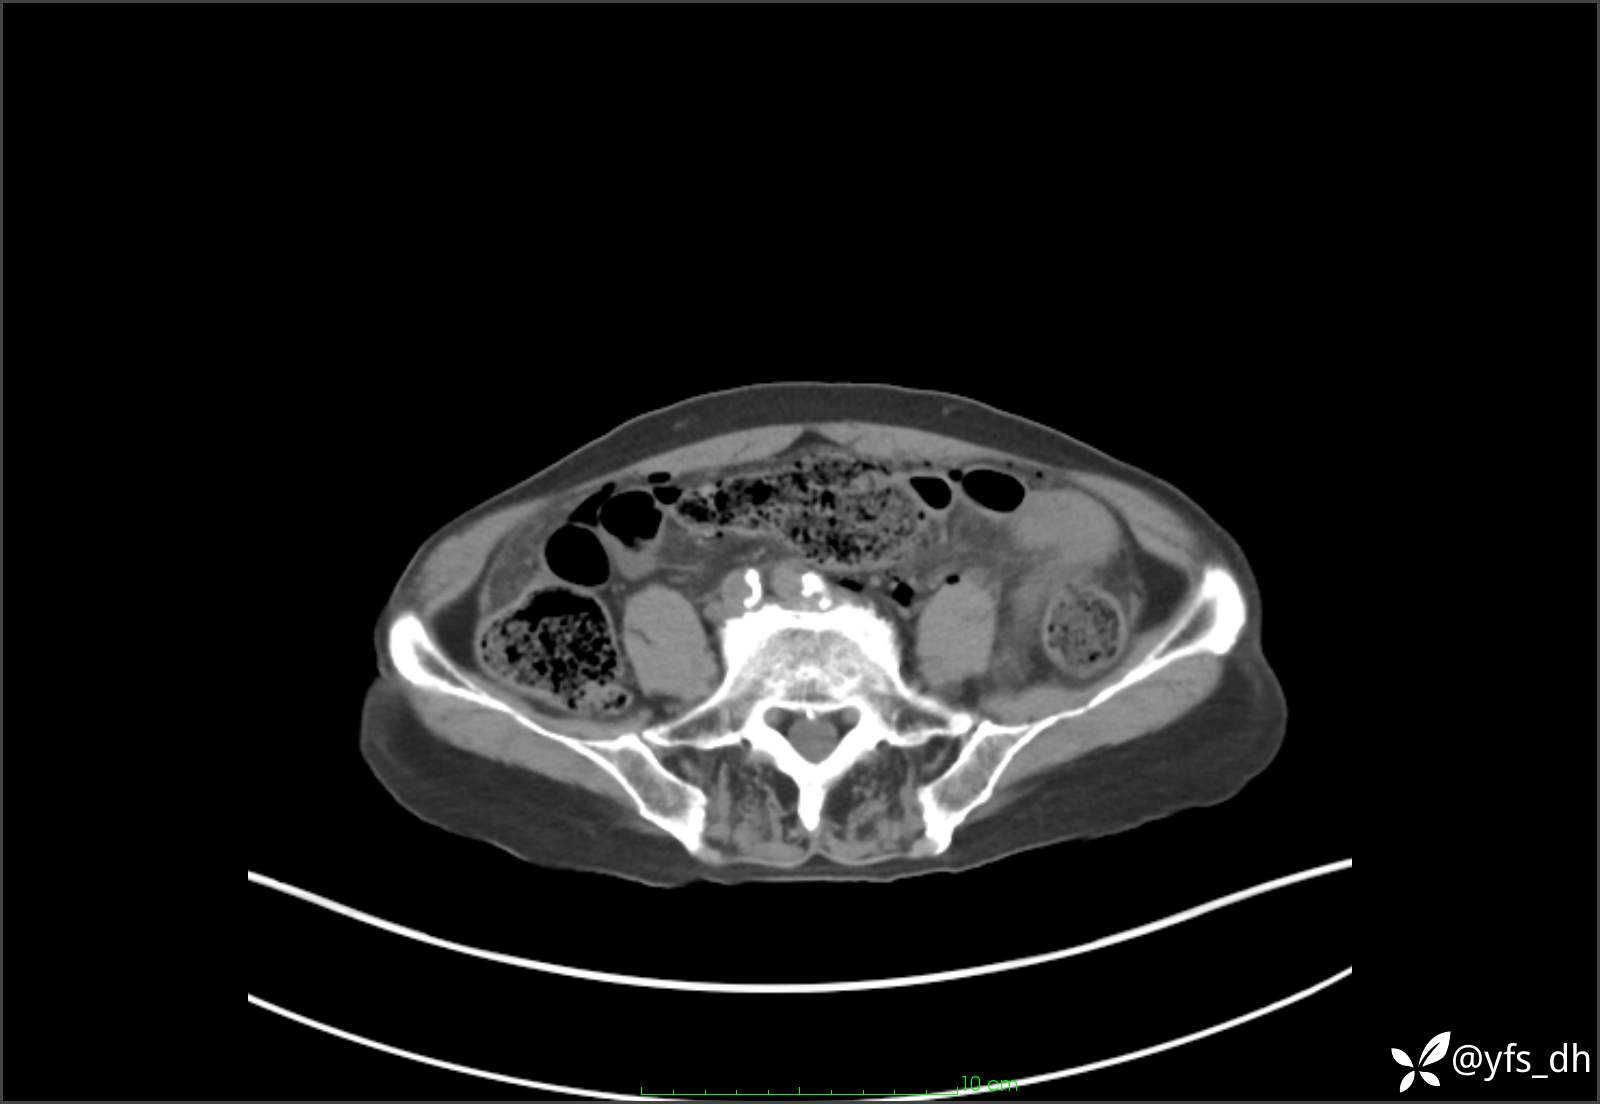

1.简要病史:患者4天前突发上腹部疼痛不适,但可以忍受。3小时前饭后突然加重,不能忍受后就诊。

2.简要手术记录:术中见腹盆腔大量肠液及粪便,乙状结肠中下段见一约3cm的破口。